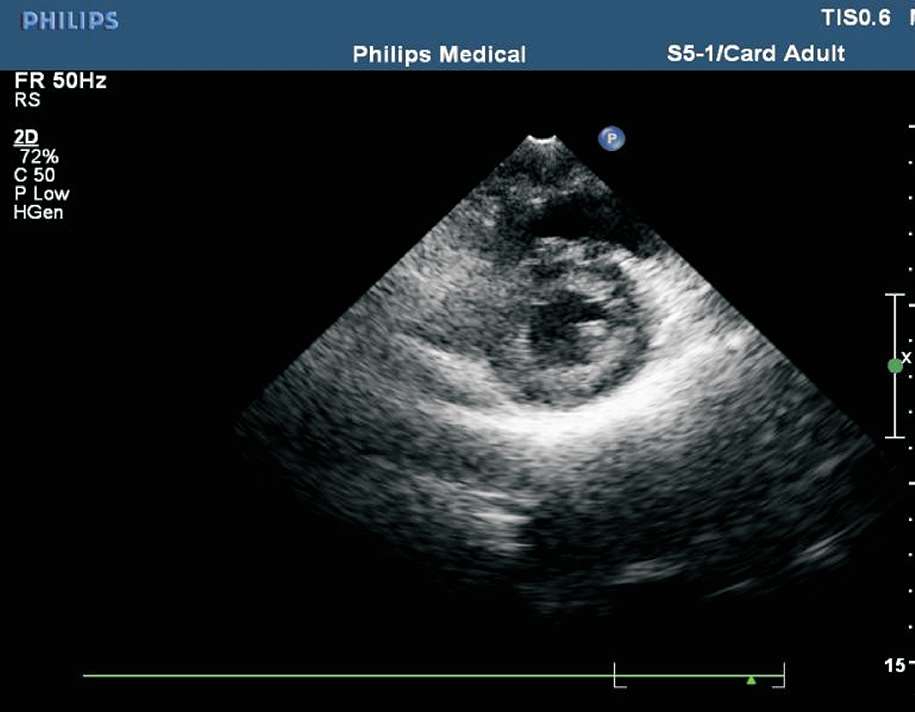

患者取左侧卧位或平卧位,探头置于胸骨左缘第2~3 肋间,声束垂直于胸骨旁左心室长轴切面。在此切面可观察主动脉瓣的形态、厚度、回声强度及开闭状态,右心室流出道与肺动脉干有无增宽、狭窄,降主动脉与肺动脉之间有无异常通道,肺动脉瓣的形态及活动(见图1-27)。正常主动脉瓣呈三瓣叶,收缩期开放为“▽”形,舒张期关闭为“Y”形(见图1-28)。

图1-27 心底大动脉短轴切面(RA:右心房;RV:右心室;PA:肺动脉;AO:主动脉;LA:左心房)

图1-28 心底大动脉短轴切面主动脉瓣呈三瓣叶,舒张期关闭为“Y”形